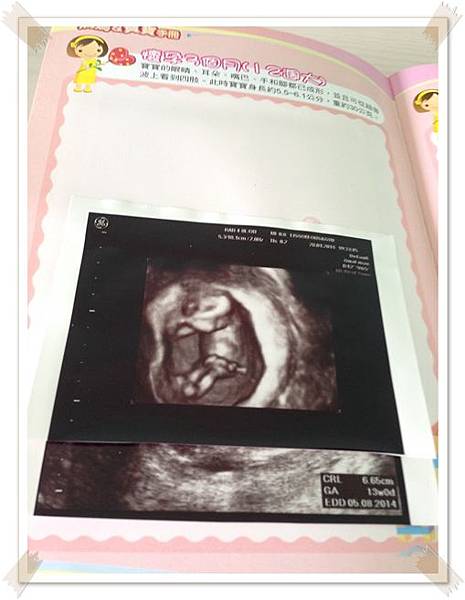

除了懷孕初期有比較常照超音波之外, 從懷孕8週起到28週都是1個月產檢一次

我說是醫生便約了下次12W回診的時間

12W我也領到媽媽手冊了越來越有當媽媽的感覺了

婦產科的超音波設備是4D的,, 只是每次醫生印了一堆給我,我都搞不清楚是身體哪個部位